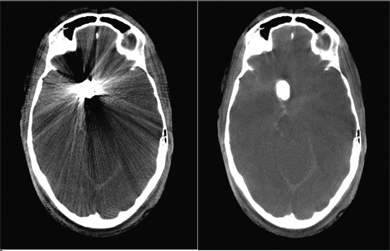

Metal objects in the patient’s body, including surgical clips or coils used in aneurysm therapy, cause massive streak metal artifacts in computed tomography (CT) or CT-like imaging as delivered using traditional syngo DynaCT. Because these streaks interfere with efforts to analyze areas of the body located near these metal objects, clinicians lack important information immediately following implantation that can help them identify complications such as hemorrhaging that can occur near the metal objects.

Siemens’ syngo DynaCT SMART algorithm removes metal streak artifacts from the image and enables visualization of regions near the metal for diagnostic purposes. The improved information content of the images helps to reduce the likelihood of errors and potentially the need for additional post-operative exams and/or hospital readmission.